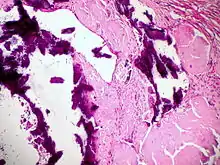

![]() Dystrophische Verkalkung (violett) bei Lymphknotenamyloidose, H&E. |